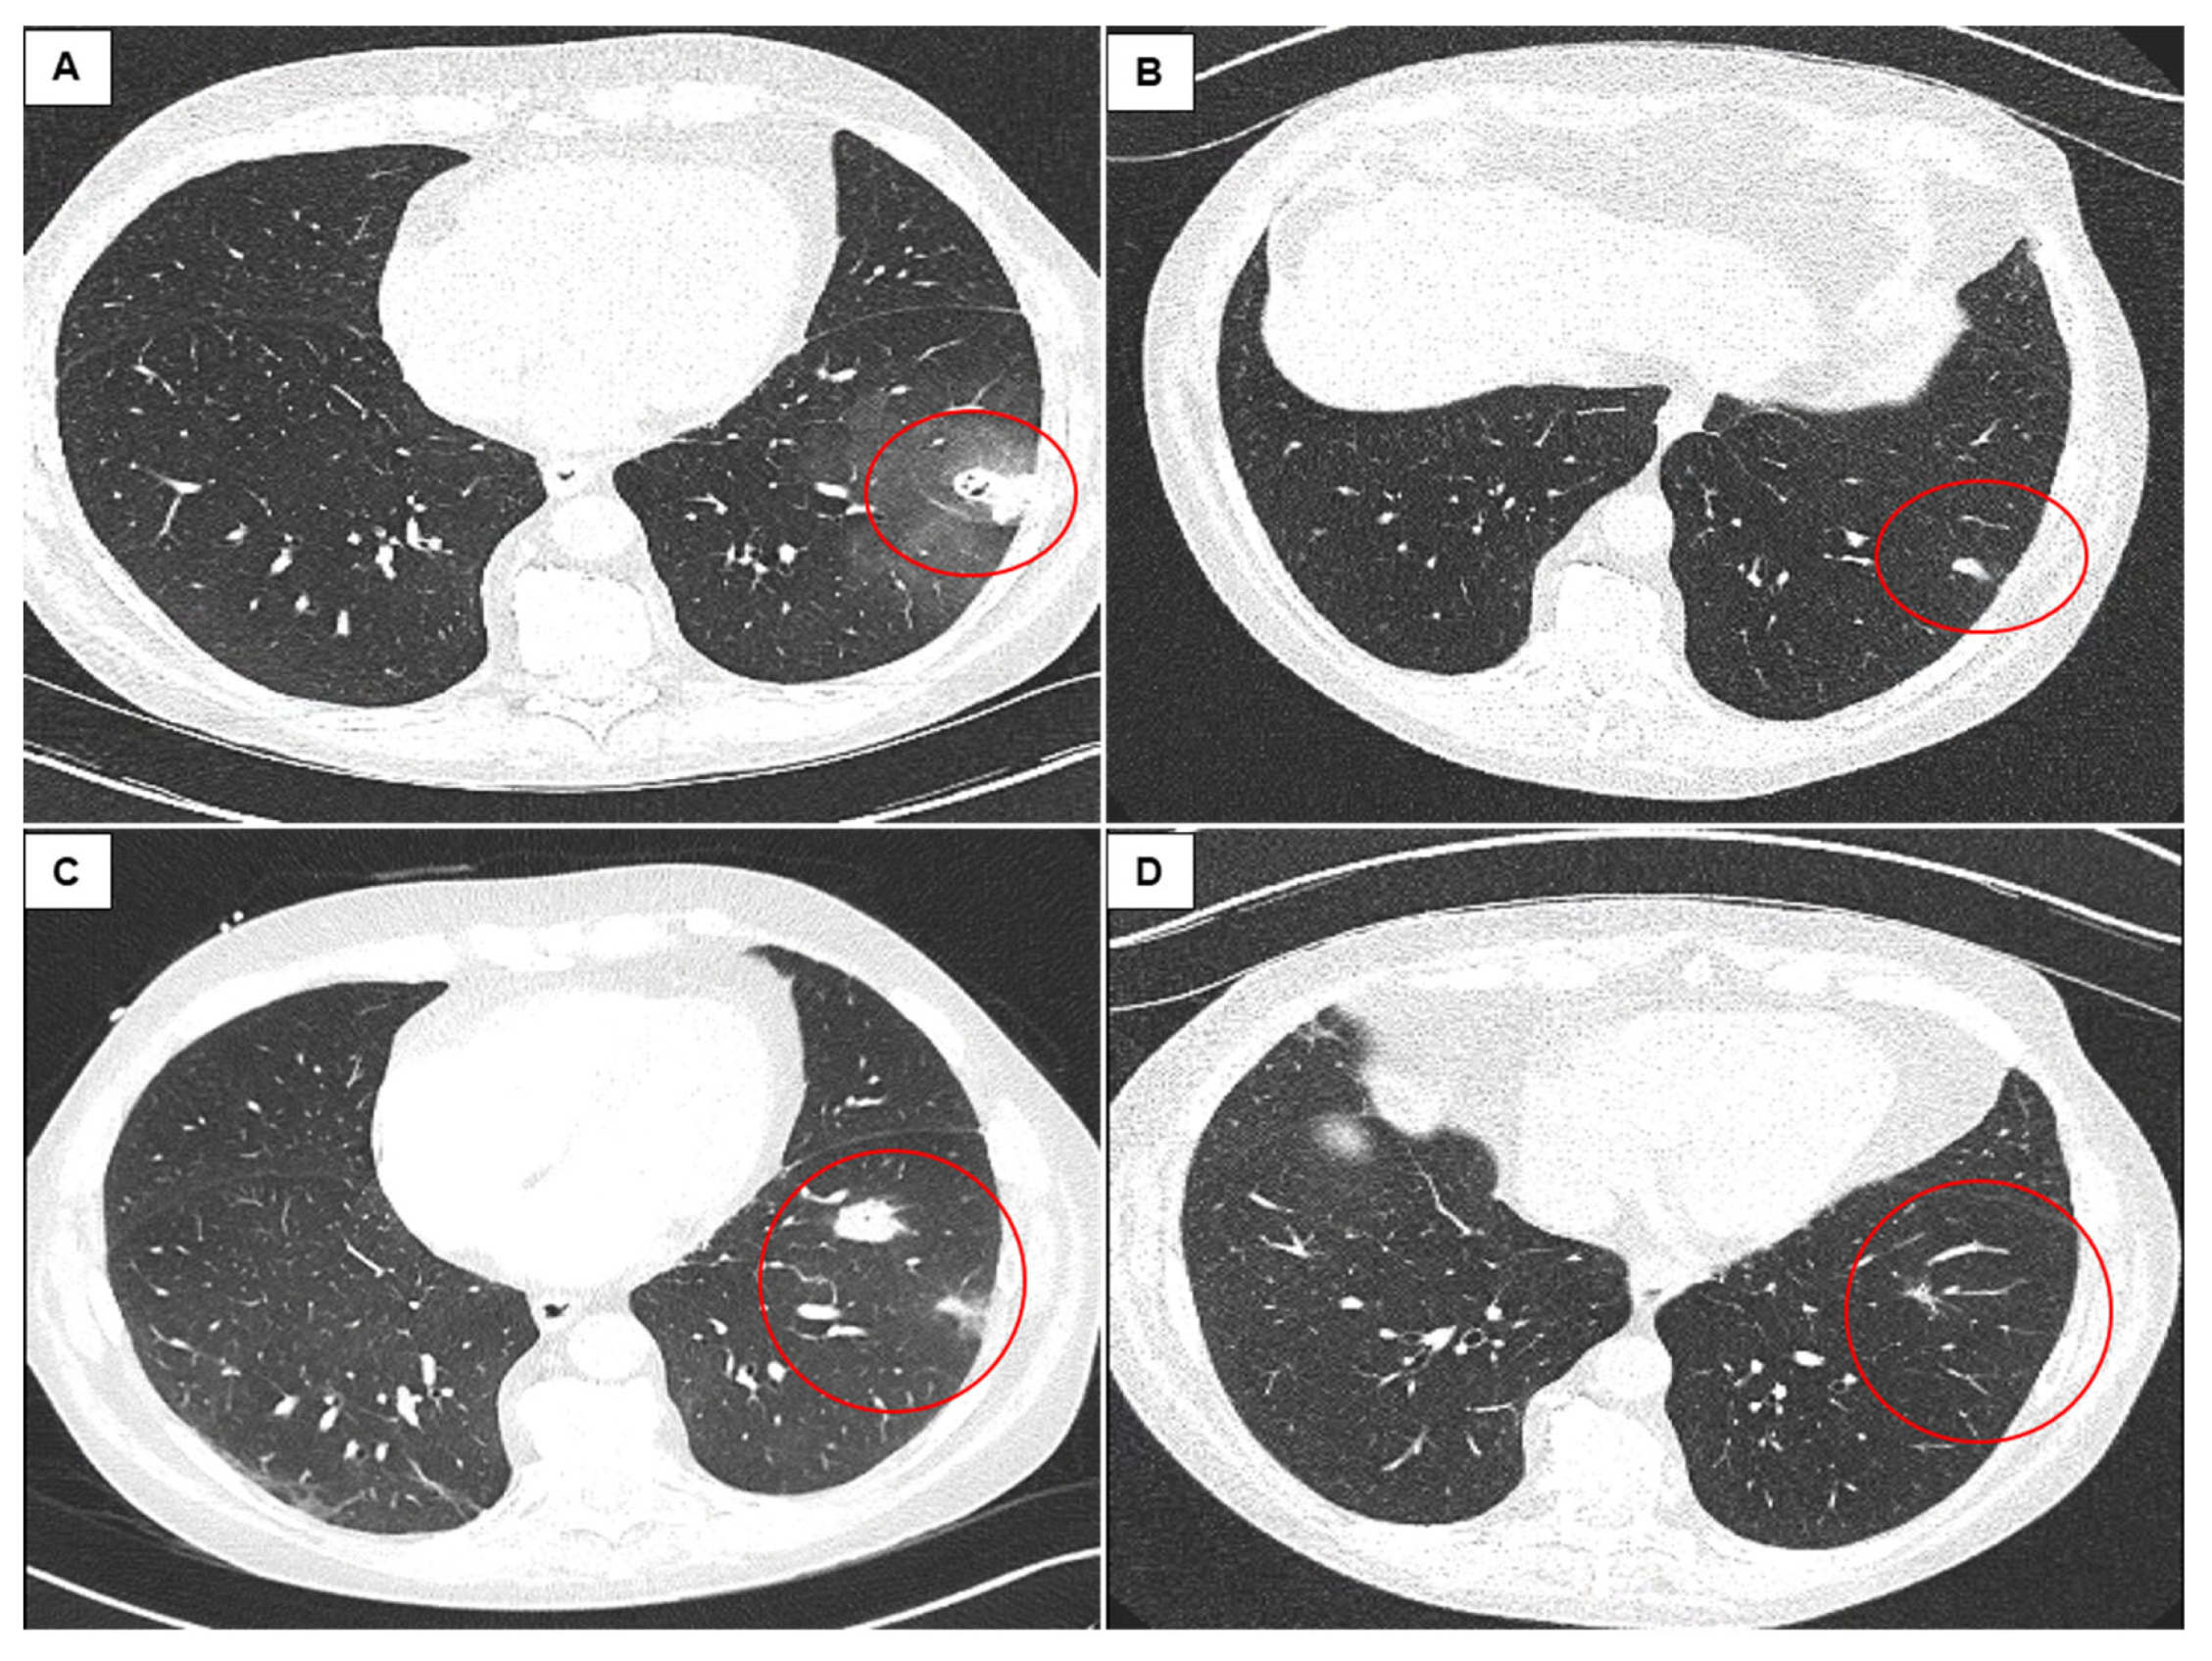

- Loor, K.; Pallisa, E.; Culebras, M.; Deu, M.; Álvarez, A.; Sansano, I.; Berastegui, C.; Clofent, D.; Polverino, E.; de Gracia, J. New opacities in lung allograft after transbronchial cryobiopsy. Respir. Med. 2020, 170, 106043. [Google Scholar] [CrossRef] [PubMed]